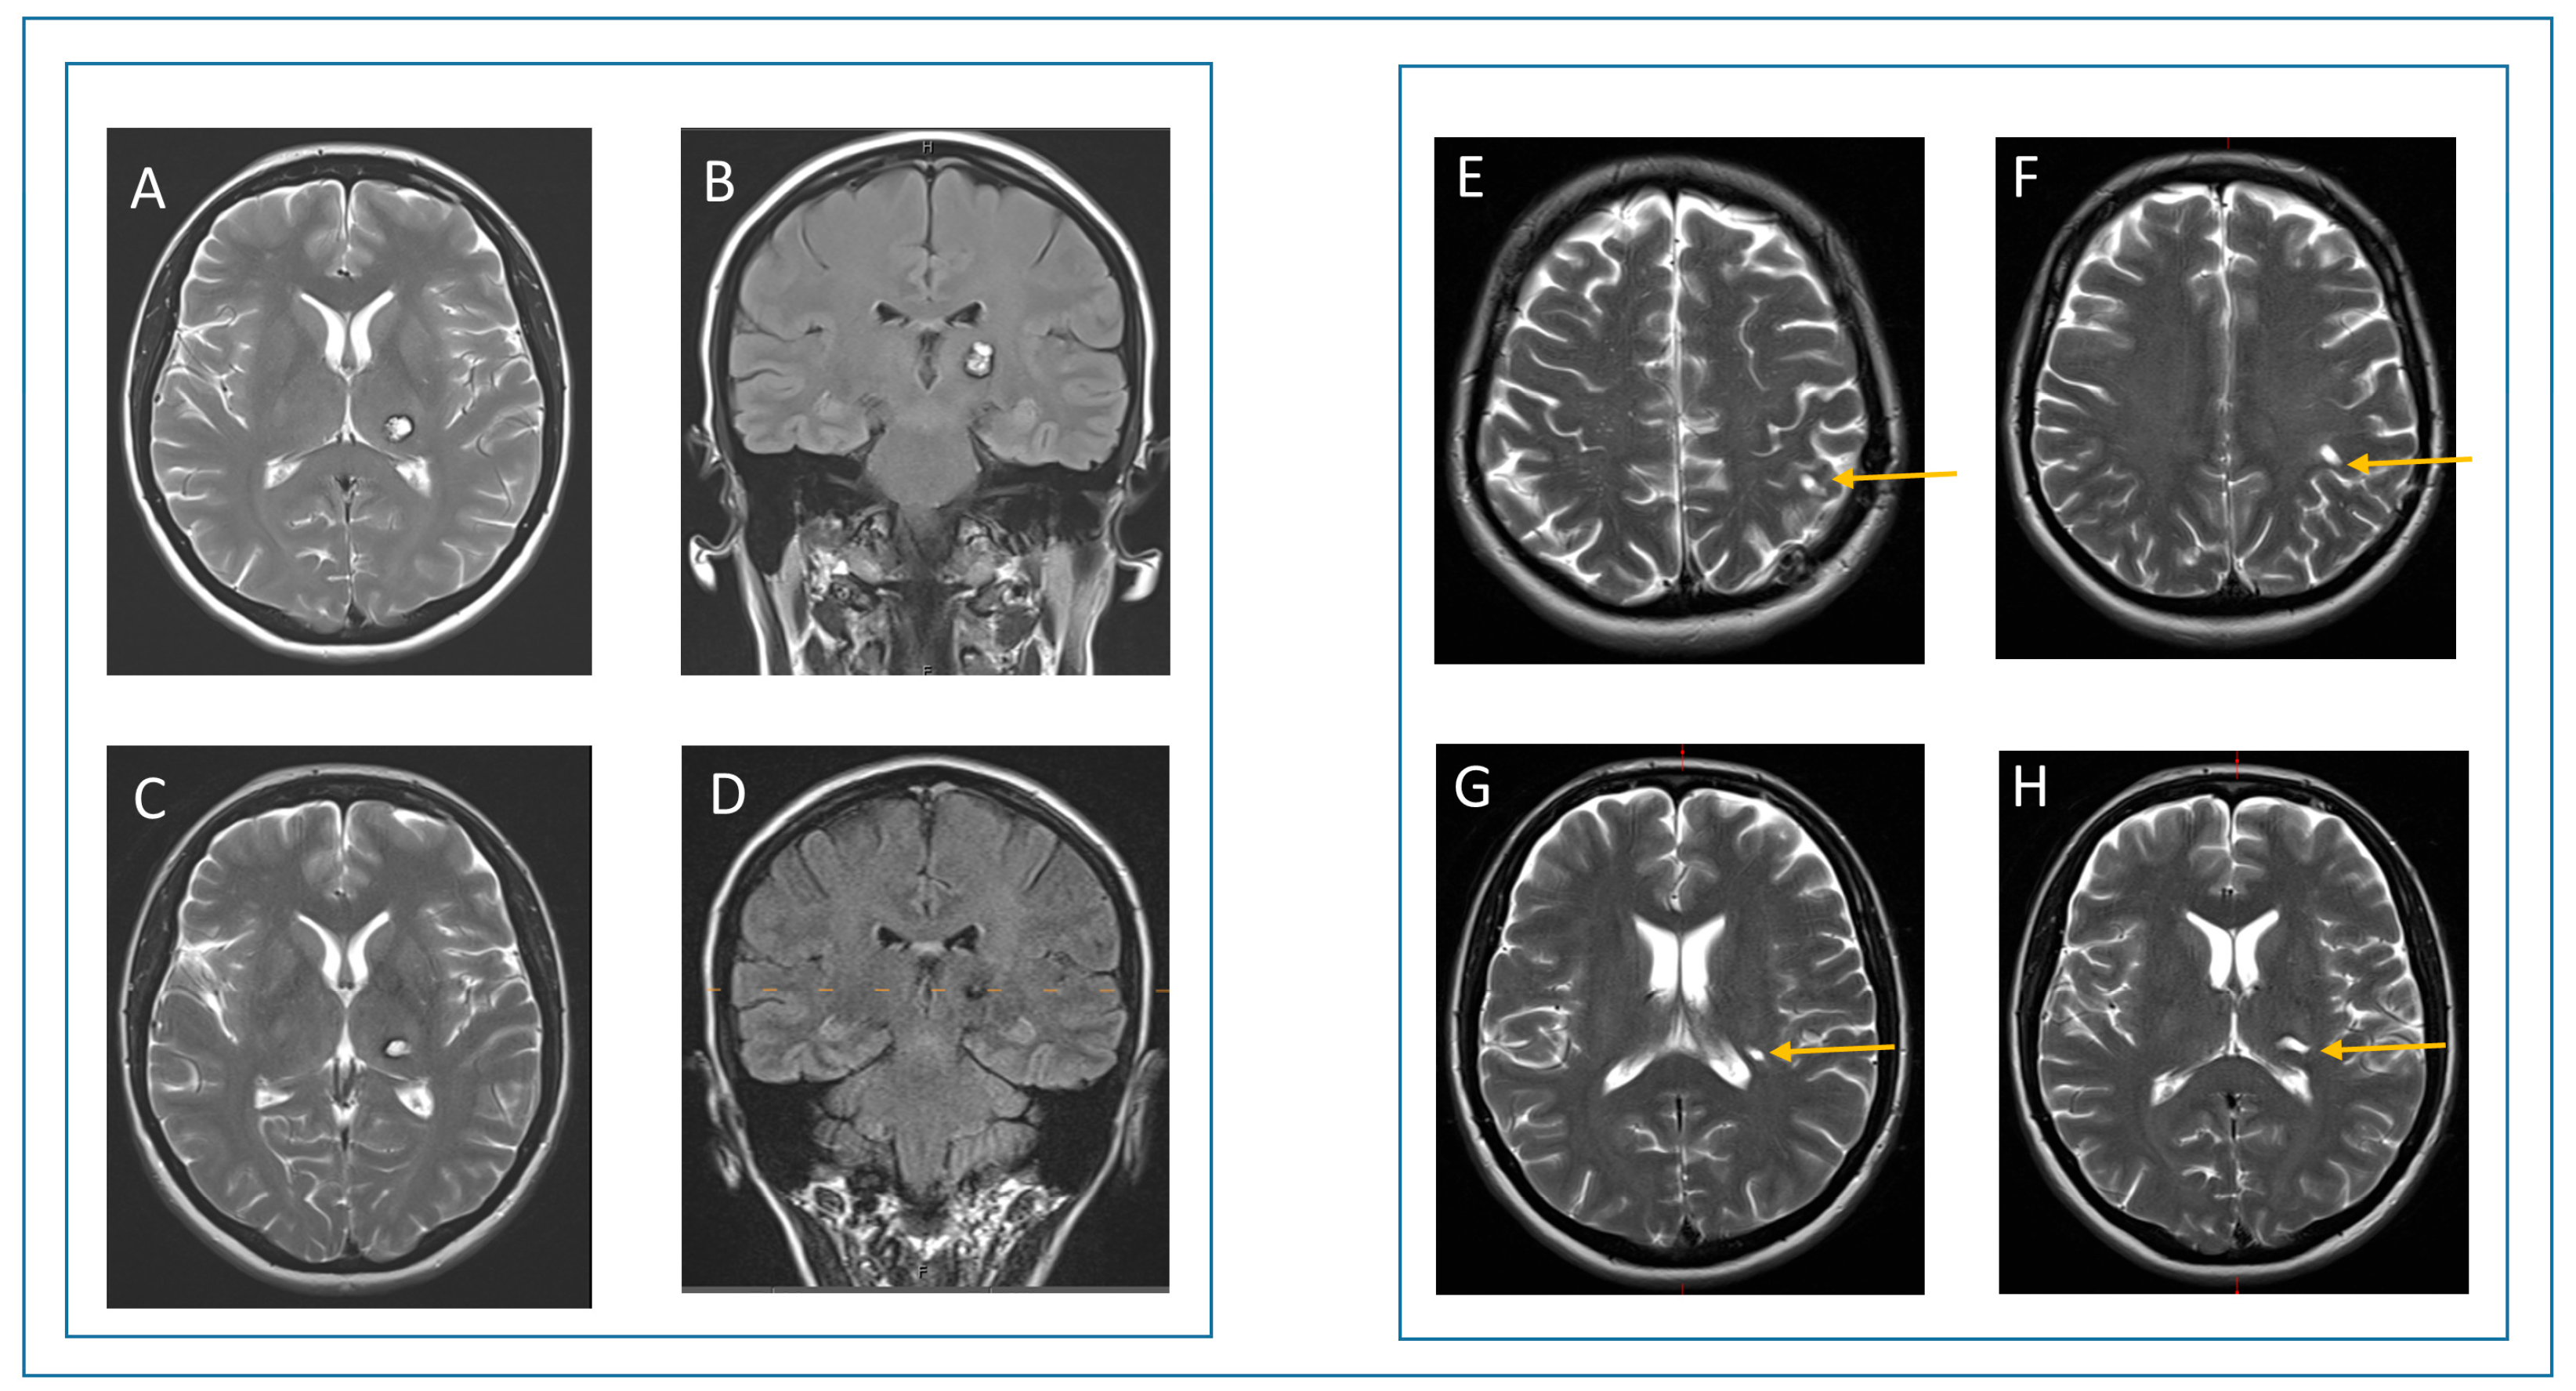

3.4. Case Report

| 3 | 16 | F | R | thalamus, cerebral crus, dorsal internal capsule | left hemiparesis (proximal 3/5, distal 1/5), hemihypesthesia | 3 | 3 | left hemiparesis (proximal 4/5, distal 2/5), hemihypesthesia improved | 2 | 4 | left hemiparesis (distal 3/5), hemihypesthesia improved | 2 | 4 |

| 4 | 66 | M | R | frontal operculum | hemihypesthesia | 1 | 4 | none | 0 | 5 | none | 0 | 5 |

| 5 | 59 | F | R | basal ganglia | no deficit (incidental finding) | 0 | 5 | none | 0 | 5 | none | 0 | 5 |

| 6 | 28 | F | R | insula, external capsule, putamen | hemihypesthesia | 1 | 4 | none | 0 | 5 | one seizure after cessation of anticonvulsants | 1 | 5 |

| 7 | 37 | F | L | eloquent superior temporal gyrus | focal seizures (expressive aphasia) | 1 | 4 | none | 0 | 5 | none | 0 | 5 |

| 8 | 27 | F | L | eloquent superior temporal gyrus | focal seizures (expressive aphasia) | 1 | 4 | none | 0 | 5 | none | 0 | 5 |

| 9 | 36 | F | R | anterior part of the insula | focal seizures (hypesthesia right arm, dysarthria) | 1 | 4 | none | 0 | 5 | none | 0 | 5 |

| 10 | 19 | M | R | trigonum | no deficit (incidental finding) | 0 | 5 | none | 0 | 5 | none | 0 | 5 |

| 11 | 52 | F | L | thalamus | hypesthesia right arm | 1 | 4 | transient right hemiparesis (2/5), hypesthesia right arm | 3 | 3 | none | 0 | 5 |

| 12 | 46 | F | R | splenium | focal seizures | 1 | 5 | none | 0 | 0 | none | 0 | 5 |